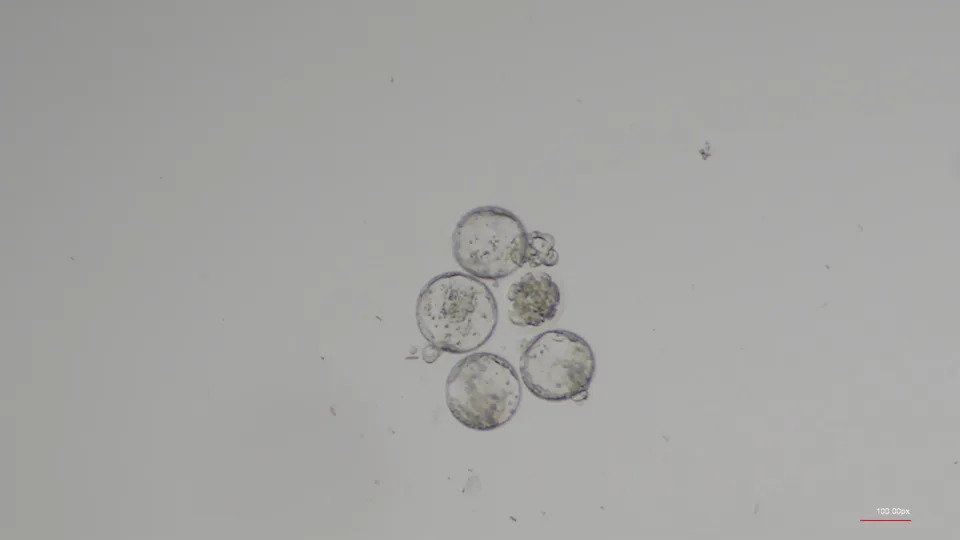

Can humans have babies in space? It may be harder than expected